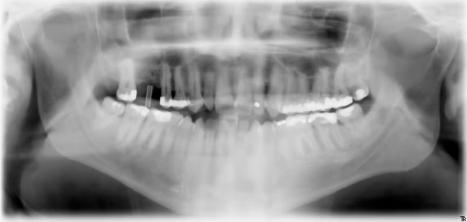

Für ein Implantat werden sowohl eine Mindestknochentiefe als auch ein Sicherheitsabstand im Unterkiefer zum Nervenkanal vorausgesetzt. Die Knochentiefe wird durch spezielle Röntgendiagnostik ermittelt.

Die reale Knochenhöhe wird mit Hilfe einer Röntgenschablone ermittelt. Bei unserem digitalen Röntgengerät kann gegebenenfalls auf die Messschablone in Einzelfällen verzichtet werden, da es über ein integriertes Messtool verfügt. Zur Detailabklärung kann es erforderlich sein, zusätzliche Aufnahmen von einzelnen Zahnabschnitten zu machen.

Panorama-Röntgenaufnahme - Implantat im Oberkiefer